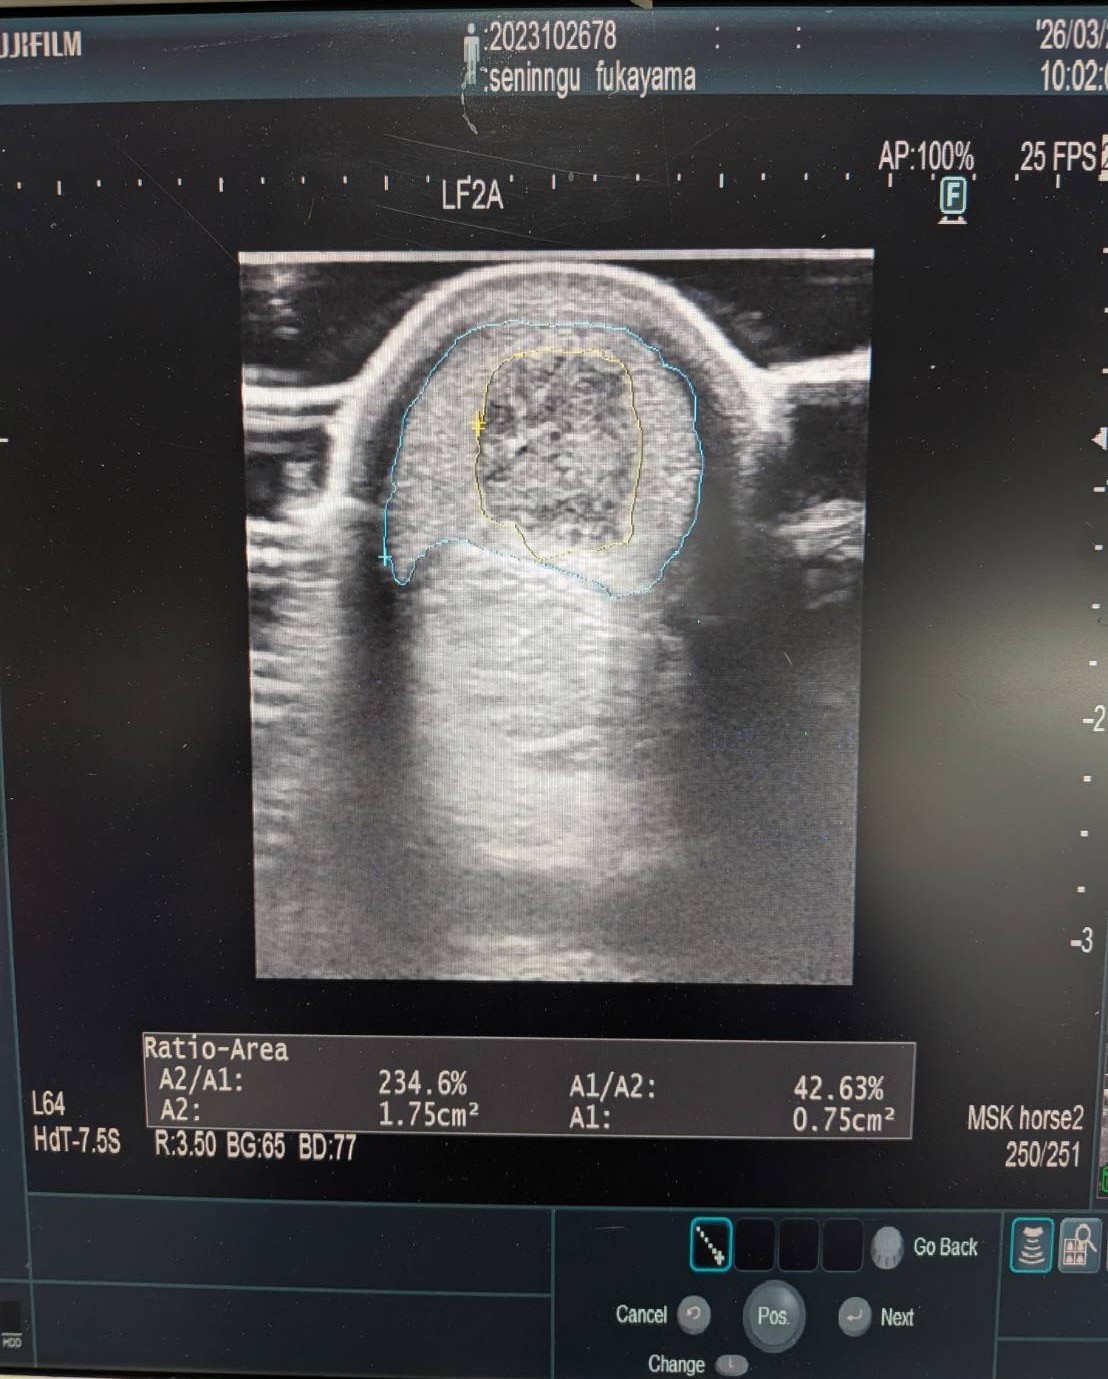

同馬は2024年のセレクションセール上場馬。北海道で馴致・育成を行い順調に調整が進んだ後、2歳の3月下旬に美浦近郊へ移動し、3月末に美浦トレセンへ入厩。4月前半にはゲート試験に合格し、一度近郊での再調整を挟んで6月の東京・芝1600m戦でデビューしました。デビュー戦では先行力を見せたものの直線で伸びを欠き、その後の福島・芝1800m戦でも結果が出なかったため、秋競馬に向けて小休止。その後11月の東京・ダ1600戦からダート路線に転向すると成績は上向き、直近の3走は全て掲示板に入るなど、初勝利まであと一歩のところまで到達しました。レースぶりとしてはスタートセンスに優れ、先行・差しどちらにも対応可能な自在性が強み。実際に前々走は先行、前走は控える競馬と、展開に応じた立ち回りができる点も評価できます。また、馬体重は競走時で440~450kg台ながら、放牧中は500kg近くまで増えることから、体質の成長に伴うさらなるパフォーマンス向上も見込まれ、これまでの内容からもダート適性は明確です。一方で、前走後の検査で左前肢に屈腱炎(損傷率42%)を発症していることが判明。この状況を踏まえ、今後を検討した結果オークションへの出品となりました。現状では即戦力とは言えませんが、これまでの競走内容に加え、母系の繁殖実績の高さから、将来的には繁殖牝馬としての価値も十分に見込め、今シーズンの種付けにも間に合うタイミングです。なお、怪我の詳細については添付の写真およびエコー検査結果をご確認頂ければと思いますが、気になる場合は入札前に検査をお願い致します。公表事項以外に気になる疾病や悪癖は特にありませんが、記載事項に関するキャンセルには応じられず、現状渡しのノークレーム、ノーリターンでお願い申し上げます。

※2026年3月28日のレース中に左前肢屈腱炎(損傷率42%)を発症。事故見舞金18号(競馬会の施設内において発生した屈腱炎により9ヵ月以上中央競馬の競走に出走できなくなった場合)の適用を受けています。